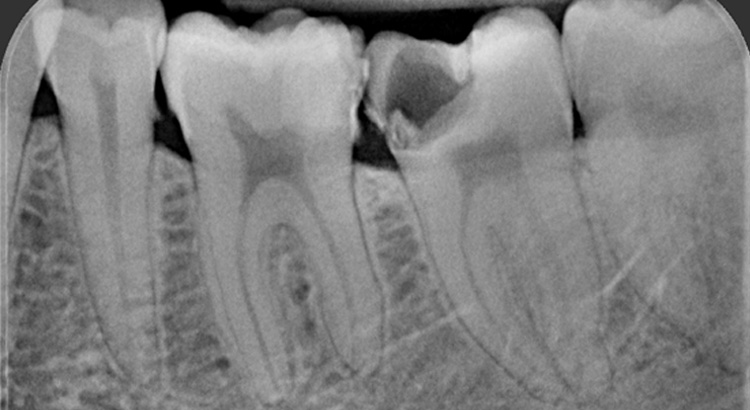

Endodonzia

Il dolore dentale è causato la maggior parte delle da una carie molto profonda che ha raggiunto o è arrivata in prossimità del nervo del dente. L’intensità del dolore può essere leggera ma costante e aumentare nel tempo, oppure può manifestarsi fin da subito con alta intesità. La disinfezione ed otturazione delle radici del dente porta al reintegro funzionale ed estetico del dente.